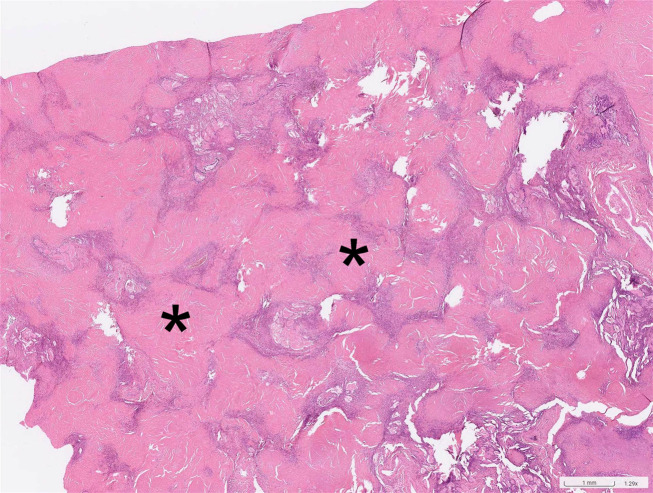

本报告重点关注在厨房台面生产中使用含有高结晶二氧化硅的人造石所带来的职业健康风险。报告一名43岁男子因从事切割和抛光石英石原料的工作而患上严重矽肺。对患者的医疗记录和职业史进行了回顾性分析。根据临床表现、肺功能检查、放射学表现和组织学报告,诊断为严重矽肺、中度限制性肺病和双侧肺气肿。患者接受了肺移植,术后肺功能有所改善。该研究强调了与人造石相关的重大健康风险,并强调了员工和工人意识和保护措施的重要性。临床医生在诊断有职业接触过含有高结晶二氧化硅的人造结石史的患者的呼吸道症状时应谨慎。

This report focuses on the occupational health risks associated with the use of artificial stones containing high levels of crystalline silica in the production of kitchen countertops. It presents the case of a 43-yr-old man who developed severe silicosis due to his occupation involving cutting and polishing quartz stone raw materials. A retrospective analysis of the patient's medical records and occupational history was conducted. The diagnosis of severe silicosis, moderate restrictive lung disease, and bilateral pneumothorax was based on clinical manifestations, pulmonary function test, radiological findings, and histological reports. The patient underwent lung transplantation, and his pulmonary function improved post-surgery. The study highlights the significant health risks associated with procedures involving artificial stones and emphasizes the importance of awareness and protective measures for employees and workers. Clinicians should be cautious when diagnosing respiratory symptoms in patients with a history of occupational exposure to artificial stones containing high levels of crystalline silica.